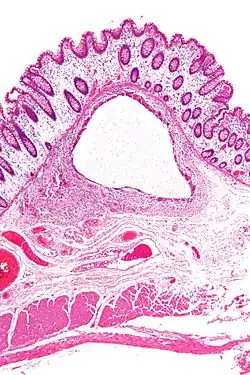

| Close-up of intestine of infant showing necrosis and pneumatosis intestinalis (autopsy) | |

Micrograph showing large bowel wall with pneumatosis cystoides intestinalis, a generally benign subset of pneumatosis intestinalis. H&E stain.

Micrograph showing large bowel wall with pneumatosis cystoides intestinalis, a generally benign subset of pneumatosis intestinalis. H&E stain.